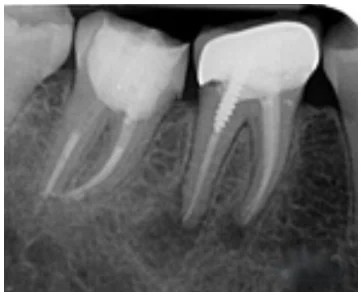

Prima e durante le cure canalari

Durante una devitalizzazione, la radiografia endorale è essenziale per valutare la lunghezza e la forma delle radici e per controllare l’efficacia del trattamento.